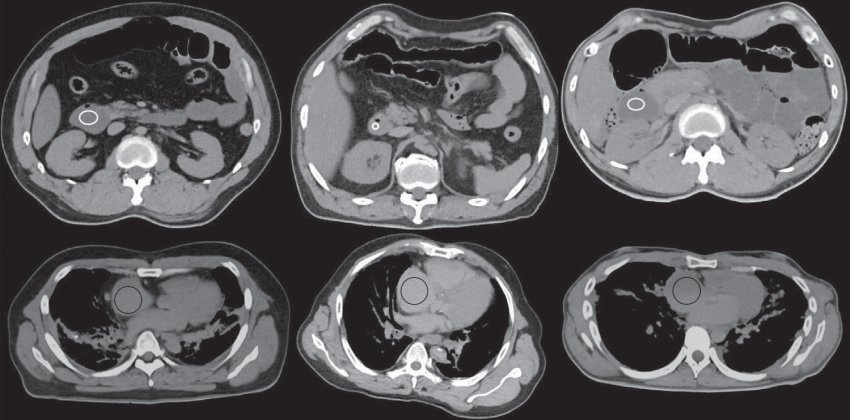

Посмертная томограмма двенадцатиперстной кишки (верхний ряд) и правого предсердия (снизу): слева отравление водой, по центру внутреннее кровоизлияние в мозг, справа утопленник